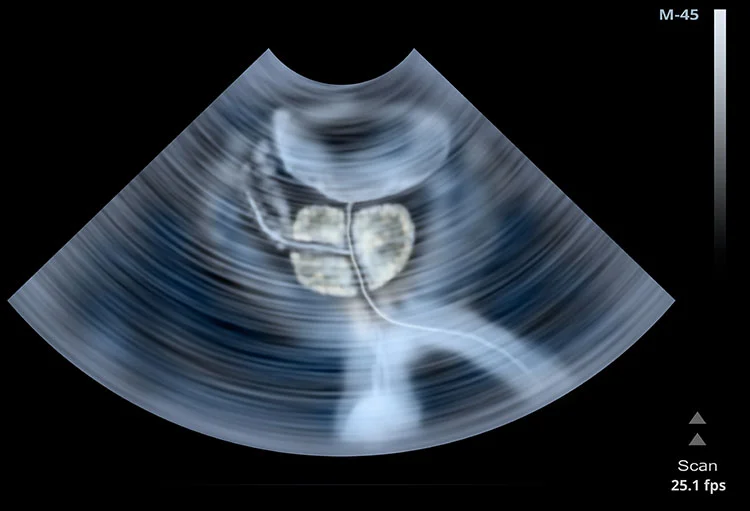

Normal Anatomy

About the size of a walnut (20 milliliters), a normal prostate is small and squishy and sits under the bladder and in front of the rectum. The urethra, a narrow tube that runs the length of the penis and carries both urine and semen, runs directly through the prostate. Just below the prostate are the seminal vesicles, which are two little glands that secrete about 60 percent of substances that make up semen. And, running alongside and attached to the sides of the prostate, are the nerves that control erectile function.